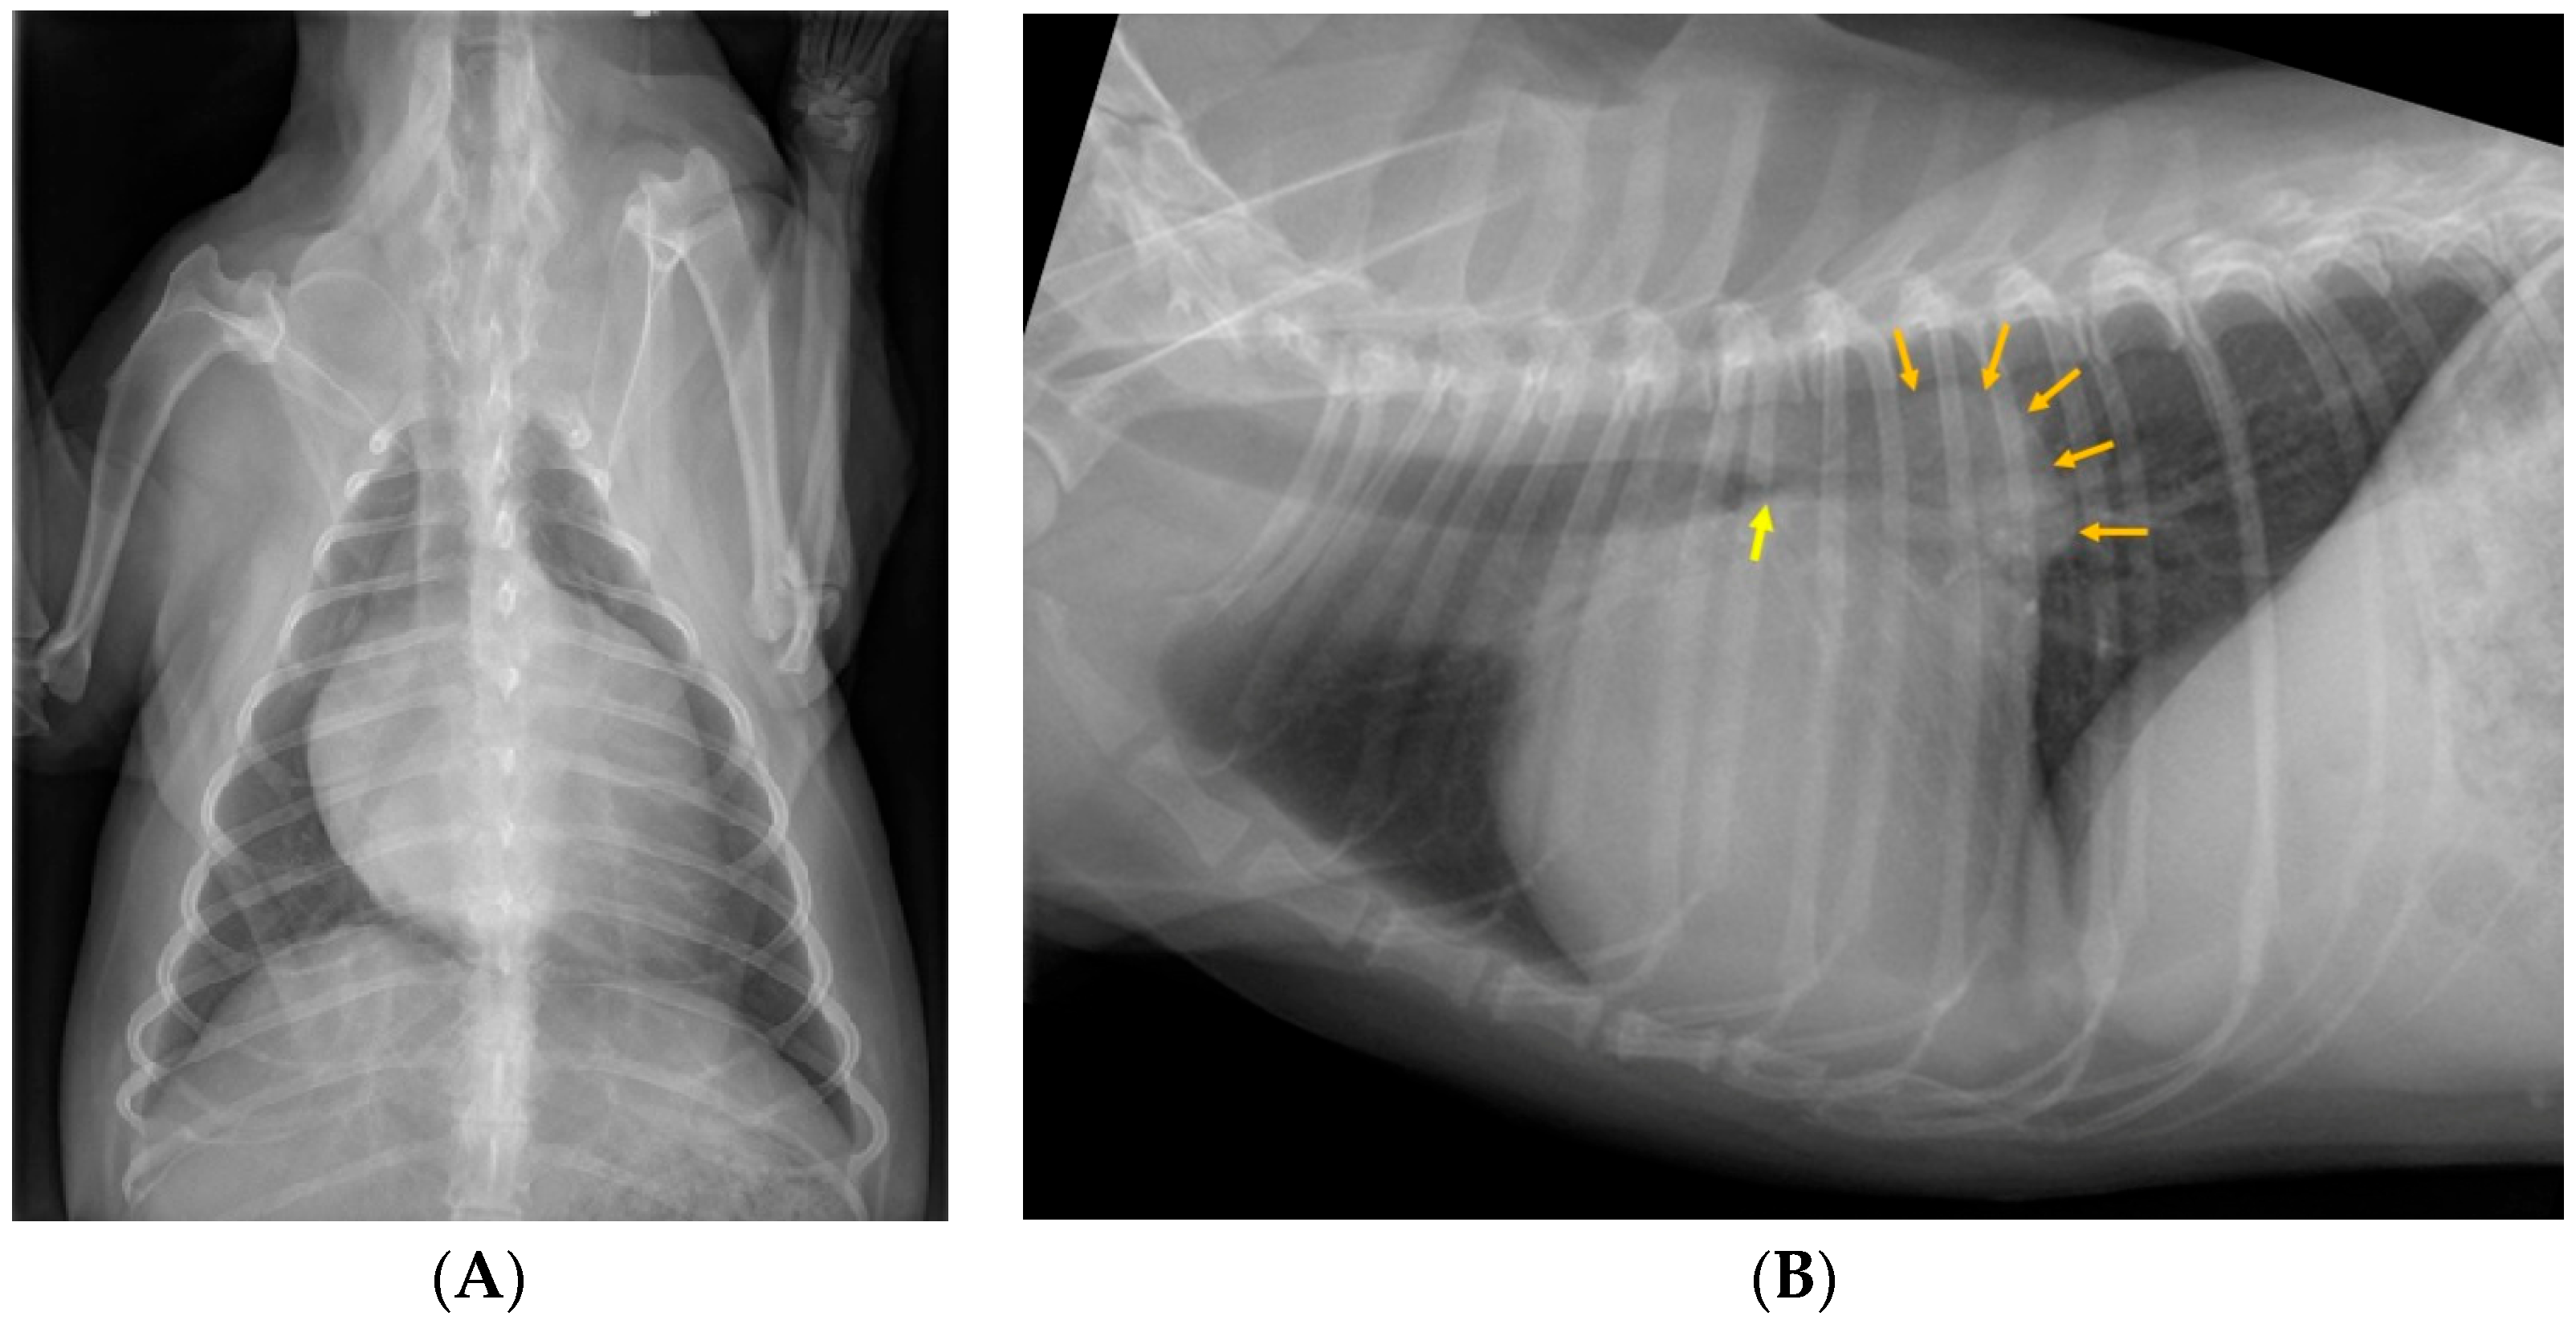

3.3. Image Review

3.4. Sensitivity and Specificity of Bronchial Compression/Collapse as a Predictor of Cough

3.5. Correlation of Radiographic Variables with Chronic Cough